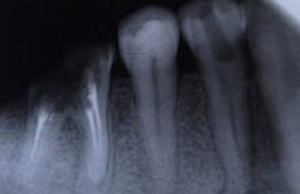

其面積為3×4平方厘米。一張牙片可以顯示3-4個牙齒。牙齒在牙片上顯示出白色阻射影像。其中牙釉質(zhì)阻射最強(qiáng),牙本質(zhì)和牙骨質(zhì)阻射低于牙釉質(zhì)。牙髓腔呈黑色透明影像,根管口至根尖孔呈逐漸變細(xì)的影像。

牙片是口腔科應(yīng)用最廣的檢查手段,也是最常用的,因?yàn)樗谘赖闹委熐啊⒅委熤泻椭委熀蠖加兄谠\斷和治療。治療前有助于發(fā)現(xiàn)病變;治療中可用插針照相方法了解擴(kuò)根情況等;治療后觀察療效等。臨床上,利用牙片對牙齒硬組織病變、牙髓病變、尖周病變及牙周病進(jìn)行診斷治療。